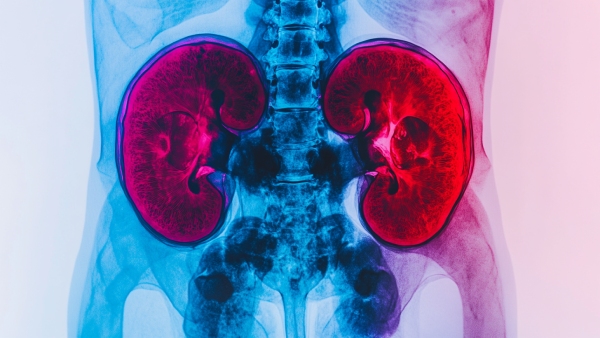

சிறுநீரகங்கள் நம் உடலின் மிகவும் முக்கியமான மற்றும் அத்தியாவசியமான உடலுறுப்பு ஆகும். உடலை தூய்மையாக வைத்திருக்கவும், ஒட்டுமொத்த ஆரோக்கியத்தை மேம்படுத்தவும் சிறுநீரகம் முக்கியமானதாகும். பொதுவாக மனிதர்கள் அனைவரும் இரண்டு சிறுநீரகங்களுடன் படைக்கப்படுகிறார்கள்.

சில மருத்துவ சூழ்நிலைகளாலோ அல்லது தவறான பழக்கங்களாலோ சிறுநீரகம் பாதிக்கப்படும் போது ஒரு சிறுநீரகத்தை அகற்றும் நிலை ஏற்படுகிறது. சிறுநீரகங்களில் ஒன்றை இழந்து விட்டால் அதன்பின் வாழ்வது என்று கூறப்படுகிறது. ஆனால் உண்மையில் நீங்கள் நினைப்பதை விட ஒன்றுடன் வாழ்வது மிகவும் எளிதானது.

பிறவி காரணங்களாலோ, அறுவை சிகிச்சை மூலம் அகற்றினாலோ அல்லது நன்கொடையாலோ, பல நபர்கள் ஒரே சிறுநீரகத்துடன் இயல்பான, சுறுசுறுப்பான வாழ்க்கையை நடத்துகிறார்கள். இருப்பினும்,சிறுநீரகம் தொடர்பாக பல கட்டுக்கதைகள் உள்ளது, இது தேவையற்ற கவலையை ஏற்படுத்துகிறது. இந்த பதிவில் சிறுநீரகம் தொடர்பான கட்டுக்கதைகள் மற்றும் உண்மைகளைப் பற்றி தெரிந்து கொள்ளலாம்.